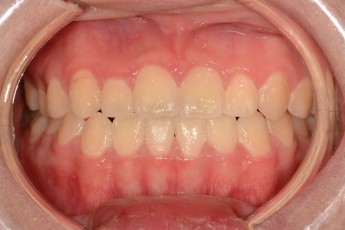

Before

After